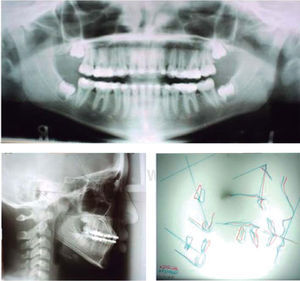

Radiográficamente la panorámica evidenció la presencia de los gérmenes de los terceros molares superiores e inferior izquierdo, niveles de crestas óseas aparentemente sano, alturas radiculares adecuadas, caninos superiores retenidos. La cefálica lateral de cráneo fue trazada con la cefalometría de McLaughlin arrojando resultados dentro de la norma siendo el único dato relevante, Witts de 9mm, permitiendo el diagnóstico de la paciente como pseudo-clase III (Cuadro I). Dedujimos que el Witts aumentado se debe al atrapamiento de la mandíbula hacia adelante por causa de la hipoplasia maxilar y el overbite aumentado causado por el recambio prematuro de los dientes deciduos.

Sus características esqueléticas, dentales y de tejidos blandos permitieron clasificar a la paciente como pseudo-clase III.

Al manipular la mandíbula se pudo lograr una relación incisal borde a borde. Por esta razón se consideró que la maloclusión tenía un componente postural «pseudo-clase III».